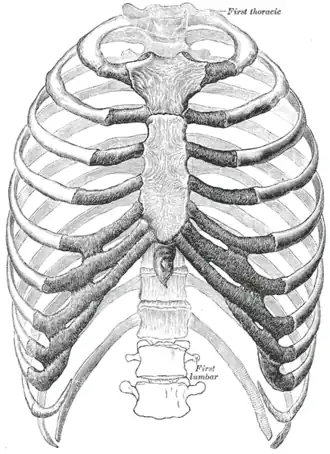

The human rib cage. | |